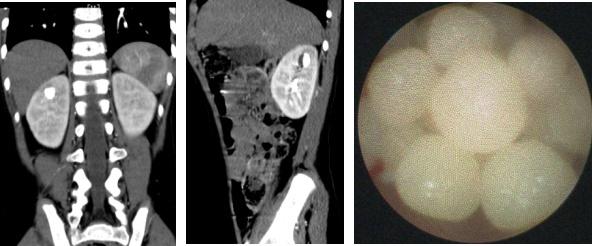

病例2:6岁男孩,马蹄肾,左肾盂及中下盏内结石,采用4.